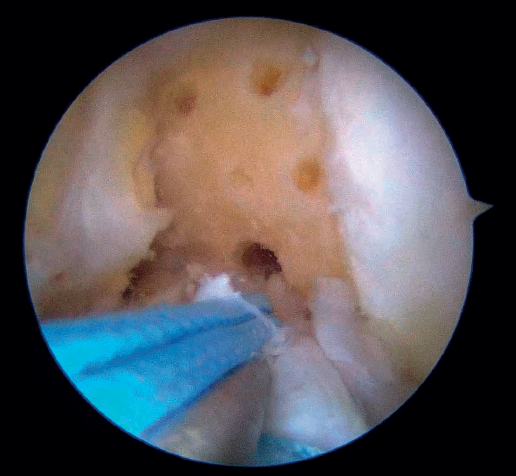

Once a good view of the central compartment is obtained, the area of the femoral footprint of the ACL is prepared to leave exposed bone, and microperforations are made in the medial wall of the lateral condyle to leave a bleeding bed to favor healing of the ligament (Figure 3). These microperforations can be made using specific instruments or with the implant punch. The advantage of using the punch is that the implant insertion site can be prepared at the same time, and only one instrument is used for the entire process (Figure 4). This step can be done after the suture has been prepared in the ligament, although doing it beforehand avoids the threads from standing in the way. The ideal point for fixation is just anterior to the native ACL footprint, although if the tear is partial or corresponds to Sherman I, it can be taken to the anatomical footprint without difficulty.

The next step consists of introducing the necessary instruments through the anteromedial portal to make several perforations approximately 1 mm deep in the femoral insertional footprint, with the aforementioned aim of obtaining a bleeding bed to facilitate healing of the ACL. Such drilling can be done manually (with micro- or nanofracture punches) or motorized (PowerPick®, Arthrex), and this step is usually made easier by flexing the knee at about 100°.